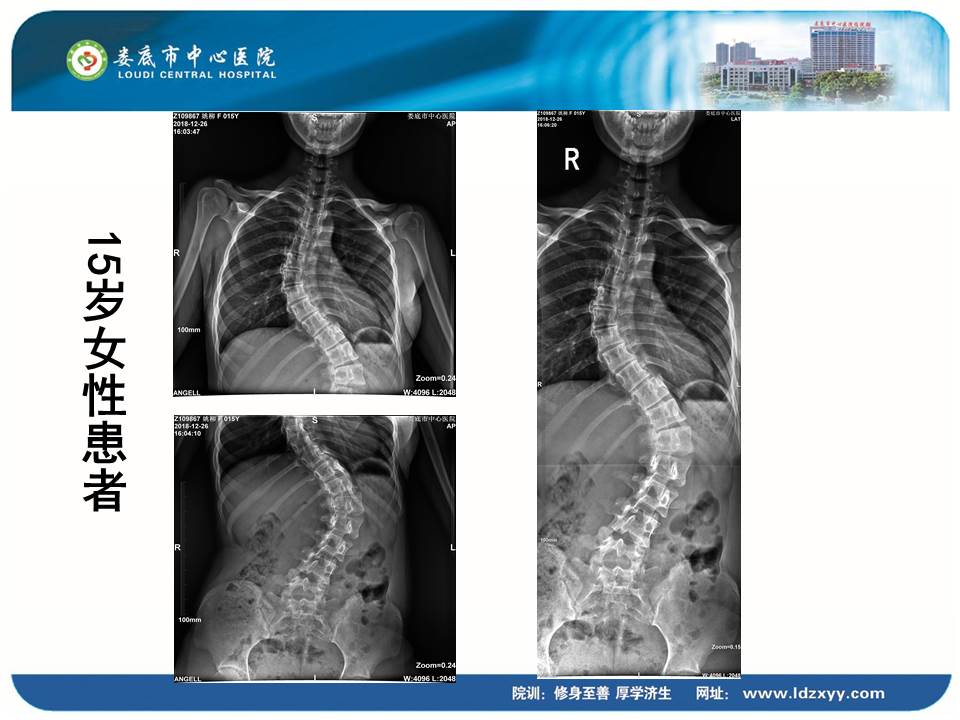

湖南影像学委员、娄底市放射学会副主任委员、娄底市中心医院放射科刘海潮副主任,则结合动态DR设备的全身拼接应用,分享了动态DR在骨科中的多项应用价值。刘海潮主任认为:由于常规DR的技术限制,长期以来放射科应用传统拍片并不能有效解决重叠部位的清晰显影,容易造成漏诊误诊,并且受制于成像视野的大小,不能有效显示脊柱四肢全长的整体结构及病变。而动态DR的17*17英寸大视野成像,配合900多万的高清像素及可视化的操作,较好地弥补了传统拍片的不足,而且初步实现了普放向精准诊断方向的转变。刘主任分享了动态DR在全脊柱摄影、全脊柱拼接、脊柱畸形,全下肢X线摄影、全下肢拼接、关节置换中的多项应用,通过站立负重位,快速、便捷摄取 2~3 张原始图像。在相邻两幅原始图像的重叠部分,对重叠图像的特征点迅速匹配,进行智能无缝融合处理,将数张有重叠部分的图像拼成一幅大型的无缝高分辨率图像。刘海潮主任评价:动态DR通过强大的图像后处理技术,比如边缘增强、灰阶处理,以及对对比度和锐利度的可调节性,大大提高了拼接影像的质量。

▲全身拼接应用示例